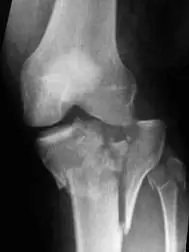

一位 45 歲健康成年男性,行走時遭汽車撞擊,左膝腫痛變形,送至急診後左膝 X光檢查結果如下圖。關於此種骨折之敘述,下列何者錯誤?

本題 X 光片為左膝關節正位影像(AP view),可見以下特徵:

- 骨折位置:脛骨近端(proximal tibia)雙髁(bicondylar)受累,呈現明顯碎裂(comminution),骨折線延伸至內外兩側脛骨平台(medial and lateral tibial plateau)

- 骨折型態:呈現 Schatzker V 型(雙髁分裂)或 VI 型(骺幹分離)外觀,骨折碎片移位明顯

- 關節面:脛骨平台關節面嚴重塌陷(articular surface depression)及不平整(incongruity),多個骨折碎片可見

- 軟組織陰影:膝關節腫脹,膝關節腔因積血(hemarthrosis)而呈密度增加

- 臨床意義:此為高能量外傷所致複雜型骨折,術前計畫需進一步影像評估以明確骨折三維形態